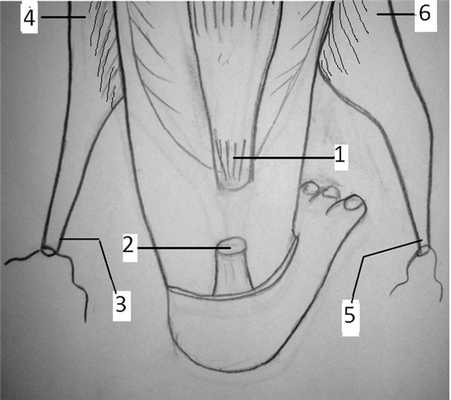

Предложенный способ иллюстрируется графическим материалом. На рис. 1 показаны Рис. 1. Выделение короткой малоберцовой и задней большеберцовых мышц. 1 — проксимальный конец ахиллова сухожилия; 2 — дистальный конец ахиллова сухожилия; 3 — сухожилия короткой малоберцовой мышцы; 4 — малоберцовая мышца; 5 — сухожилия задней большеберцовой мышцы; 6 — задняя большеберцовая мышца. проксимальный конец (1) и дистальный конец (2) ахиллова сухожилия. Выделено и взято на держалку сухожилие (3) короткой малоберцовой мышцы (4). Выделено и взято на держалку сухожилие (5) задней большеберцовой мышцы (6).